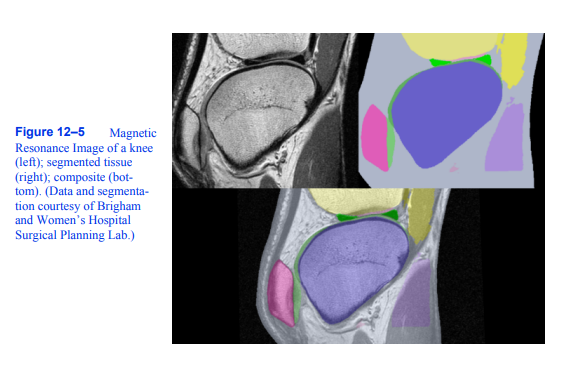

出于我们的目的,我们假设有人(或许多研究生)用组织标识符费力地标记了数据卷的每个切片中的每个像素。这个标识符是一个整数,描述每个像素属于哪个组织类。例如,我们可能会得到一系列膝盖的MRI切片,上面有定义半月板、股骨、肌肉等的组织编号。图12 - 5显示了从患者膝盖获得的体积切片的两种表示形式。左边的图像是原始的MRI切片;右边的图像包含了一些重要器官的组织标签。下面的图片是这两张图片的合成。

请注意每种表示所呈现的信息的差异。原始切片显示器官边界逐渐变化,而分割切片显示器官边界突变。在前面的CT实例中,我们处理的图像使用了行进立方体等轮廓算法和强度阈值提取等值面。我们目前的分段研究有整数标签,有一个有点任意的数值。我们在这个例子中的目标是以某种方式获取组织标签并创建灰度切片,我们可以使用之前使用的相同技术进行处理。另一个目标是展示图像处理和可视化如何在应用程序中协同工作。

图12-5磁性

膝盖的共振图像

(左);分段组织

(右);复合(底部)。(数据和分割由布莱根妇女医院提供

手术计划实验室)